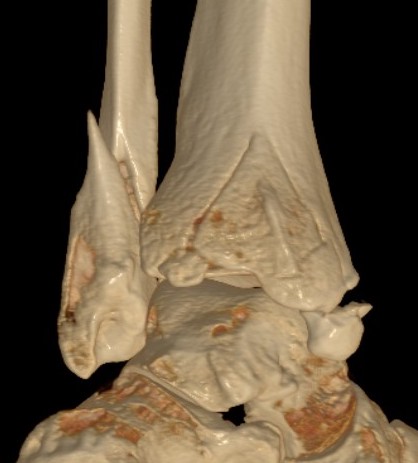

Mason and Malloy Classification

CT scan critical to classify and guide treatment / approach

| Type I | Type IIA | Type IIB | Type III |

|---|---|---|---|

| Avulsion of the PITFL |

Posterolateral fragment Volkmann fracture |

Posteromedial & posterolateral fragments Volkmann plus secondary fracture line |

Large coronal plane fragment Plafond fracture |

Issues

| Joint stability | Syndesmosis | Functional outcomes |

Large fragments - 30 - 40% Posterior joint subluxation |

PITFL attachment to posterolateral fragment Syndesmotic instability |

Evidence of improved outcomes with operative fixation Articular steps Increased contact pressures |